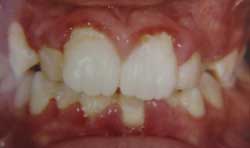

- An unhealthy smile, in which the gums pull back or recede from your teeth.

- Gums become puffy, red, and bleed when you brush or floss.

Gum disease is caused by bacteria that form into plaques on your teeth. The plaque builds up on your teeth near the gum line constantly throughout the day. The gums become swollen and red, which is the initial sign of infection. This is called gingivitis and this condition is reversible. If the plaques are not removed from the teeth on a regular basis, the bacteria move deeper into the gums progressing into an irreversible disease called periodontitis. It is at this stage when the bacteria eat away at the tissues and surrounding bone that hold your teeth in place. This stage of the disease can be arrested, but if it is not caught early enough it will result in tooth loss. Eventually, late stage periodontal disease will cause pain and your teeth will become loose.